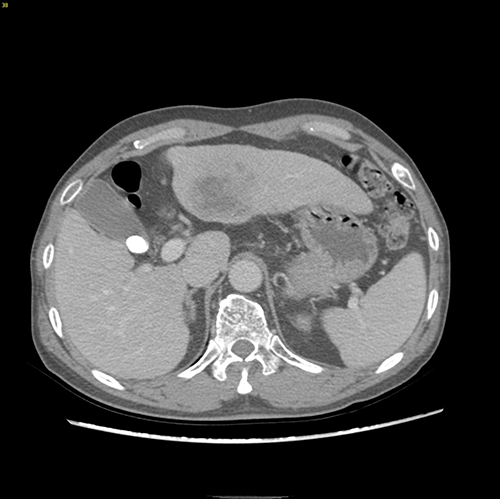

左肝外侧叶肝癌---左肝外侧叶切除